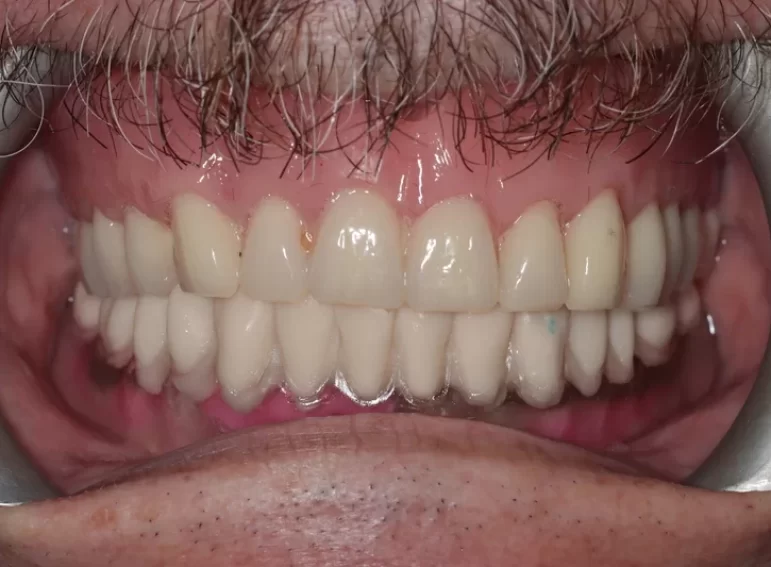

Case 37 – Implants

Upper complete denture and lower implant retained complete denture